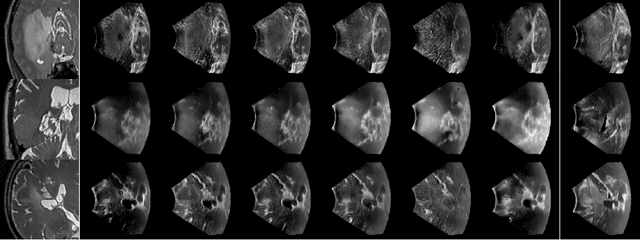

Abstract:We propose a deep mixture of multimodal hierarchical variational auto-encoders called MMHVAE that synthesizes missing images from observed images in different modalities. MMHVAE's design focuses on tackling four challenges: (i) creating a complex latent representation of multimodal data to generate high-resolution images; (ii) encouraging the variational distributions to estimate the missing information needed for cross-modal image synthesis; (iii) learning to fuse multimodal information in the context of missing data; (iv) leveraging dataset-level information to handle incomplete data sets at training time. Extensive experiments are performed on the challenging problem of pre-operative brain multi-parametric magnetic resonance and intra-operative ultrasound imaging.

Abstract:We propose in this paper a texture-invariant 2D keypoints descriptor specifically designed for matching preoperative Magnetic Resonance (MR) images with intraoperative Ultrasound (US) images. We introduce a matching-by-synthesis strategy, where intraoperative US images are synthesized from MR images accounting for multiple MR modalities and intraoperative US variability. We build our training set by enforcing keypoints localization over all images then train a patient-specific descriptor network that learns texture-invariant discriminant features in a supervised contrastive manner, leading to robust keypoints descriptors. Our experiments on real cases with ground truth show the effectiveness of the proposed approach, outperforming the state-of-the-art methods and achieving 80.35% matching precision on average.

Abstract:Intraoperative ultrasound (iUS) imaging has the potential to improve surgical outcomes in brain surgery. However, its interpretation is challenging, even for expert neurosurgeons. In this work, we designed the first patient-specific framework that performs brain tumor segmentation in trackerless iUS. To disambiguate ultrasound imaging and adapt to the neurosurgeon's surgical objective, a patient-specific real-time network is trained using synthetic ultrasound data generated by simulating virtual iUS sweep acquisitions in pre-operative MR data. Extensive experiments performed in real ultrasound data demonstrate the effectiveness of the proposed approach, allowing for adapting to the surgeon's definition of surgical targets and outperforming non-patient-specific models, neurosurgeon experts, and high-end tracking systems. Our code is available at: \url{https://github.com/ReubenDo/MHVAE-Seg}.